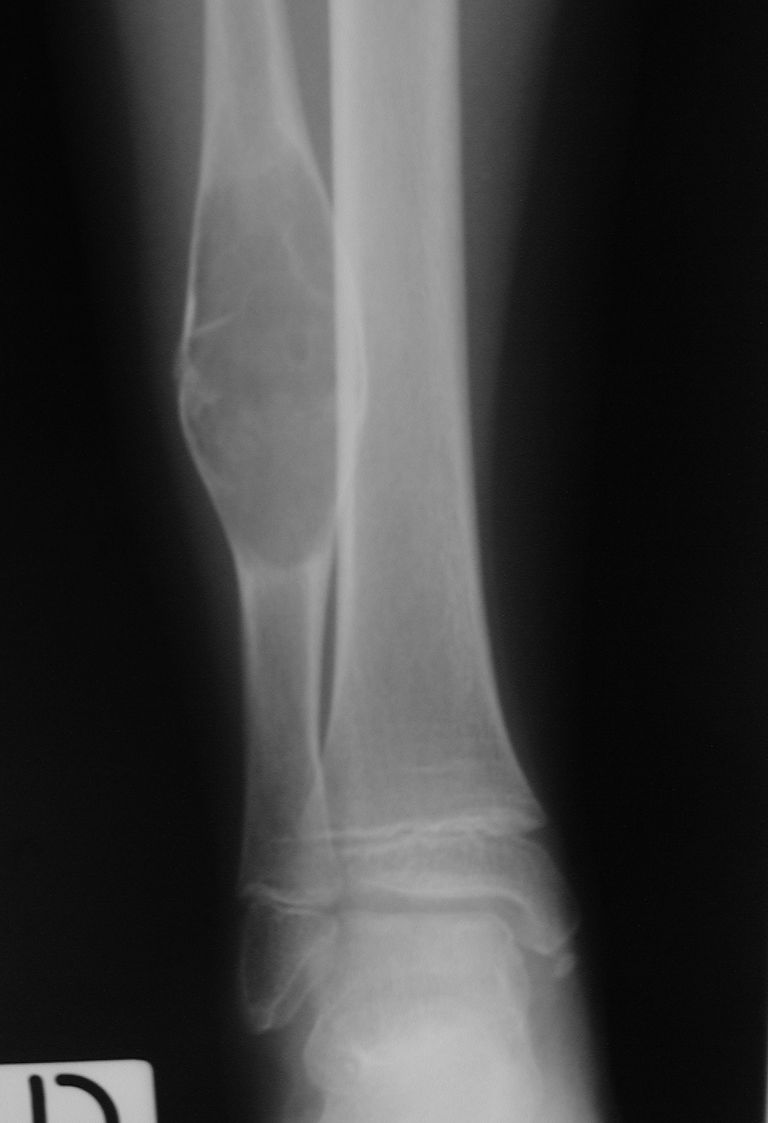

In questi casi ci troviamo di fronte a una frattura patologica su cisti ossee; anche in questi casi il reperto è occasionale dopo un trauma minimo accidentale. Possono riscontrarsi in varie parti del corpo, normalmente a carico delle ossa lunghe quali omero ( immagine a lato)  oppure in sede peroneale ( caso in basso ).